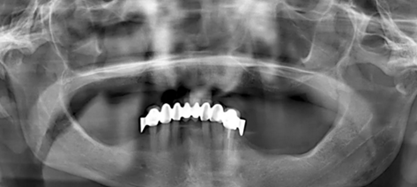

為了最大程度利用現(xiàn)有骨量,需要一個(gè)全程引導(dǎo)式的種植外科手術(shù)導(dǎo)板。在“以修復(fù)為導(dǎo)向”的方案設(shè)計(jì)過(guò)程中,根據(jù)CBCT數(shù)據(jù),對(duì)種植體與基臺(tái)中心軸向之間可能的最大夾角進(jìn)行計(jì)算。同時(shí),計(jì)劃拔除 21 牙位之前未發(fā)現(xiàn)的殘根。該牙根之所以至今才檢測(cè)到,是因?yàn)榍鏀鄬悠?(OPG) 上呈現(xiàn)出影像重疊(圖 1)。

(圖1)